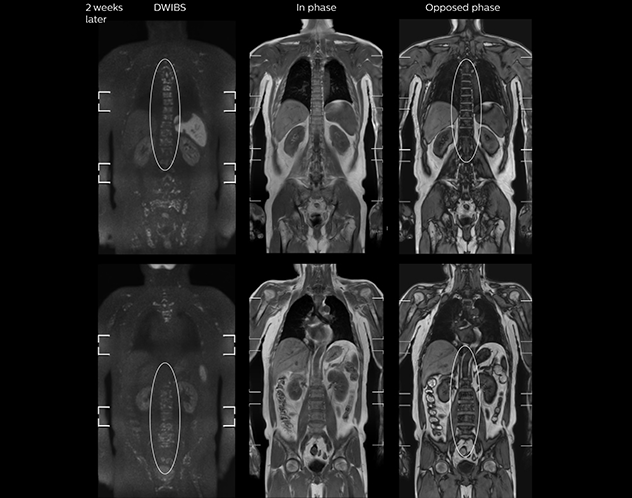

“When we limited the scan coverage to the area from neck to femur, we could fit more clinical information in approximately the same scan time. So, we added coronal mDIXON, sagittal T1-weighted, and sagittal STIR sequences to our examination, instead of performing only axial DWIBS and coronal single-shot TSE scans.” The single shot T2-weighted TSE images are used for morphology and compared to DWIBS images to identify T2 shine-through. Sagittal STIR images are used in patients with inflammation or bone metastasis.

“Switching to coronal DWIBS – rather than axial – further shortens scan time,” says Mr. Naka. “Important is that a dS SENSE factor of 5 shortens exam time while high image quality can be maintained, thanks to Ingenia’s dStream architecture.” He adds that the coronal orientation also avoids artifacts that are specific to combining axial images.

“mDIXON FFE allows us to quickly get information we need to assess the presence of fat. That gives us more information when we need to diagnose bone lesions, and when we are asked to judge fat-containing lesions such as hepatocellular or renal carcinoma,” Dr. Nobusawa says. “The mDIXON fat images can help us to differentiate fatty bone marrow from bone lesions. This is especially useful in elderly people, who tend to have fattier bone marrow. The water images provide a high signal-to-noise ratio in the intestinal canal, which is valuable for visualizing lesions in the colon,” he says.

Kawasaki Sawai Hospital’s whole body protocol also includes an mDIXON FFE sequence. Because mDIXON provides images for four contrast types – water only, fat only, in-phase and out-of-phase – from a single acquisition, it is useful in many ways.

“In-phase and out-phase sagittal T1-weighted FFE images help us to visualize and further characterize bone lesions such as metastasis and bone-marrow hyperplasia that have high signal on DWI. These images are also used throughout radiotherapy, to monitor changes in the fatty bone marrow.”